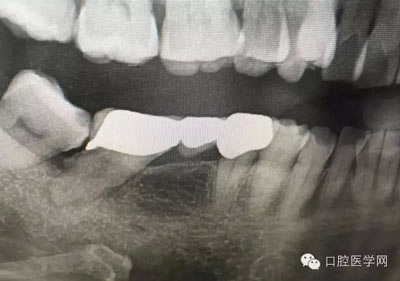

這是一例外院樹脂修復后十個月出現(xiàn)牙髓炎癥狀的患者。遇到這樣子的患者大家會怎么做,證明選擇,還有就是可做可不做治療的如何去平衡。